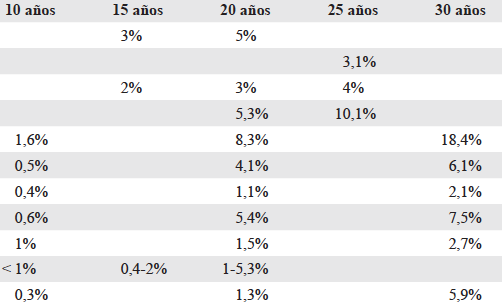

Julio César Núñez Villegas, Sergio Mauricio Rubel Cohen, Gabriel Alfredo Cavada Chacón, Laura Segovia González, Carlos Luis Matus Floody, Antonio Sa Cunha, Vilma Rodriguez, Rodrigo Abularach Cuellar

|

|

|